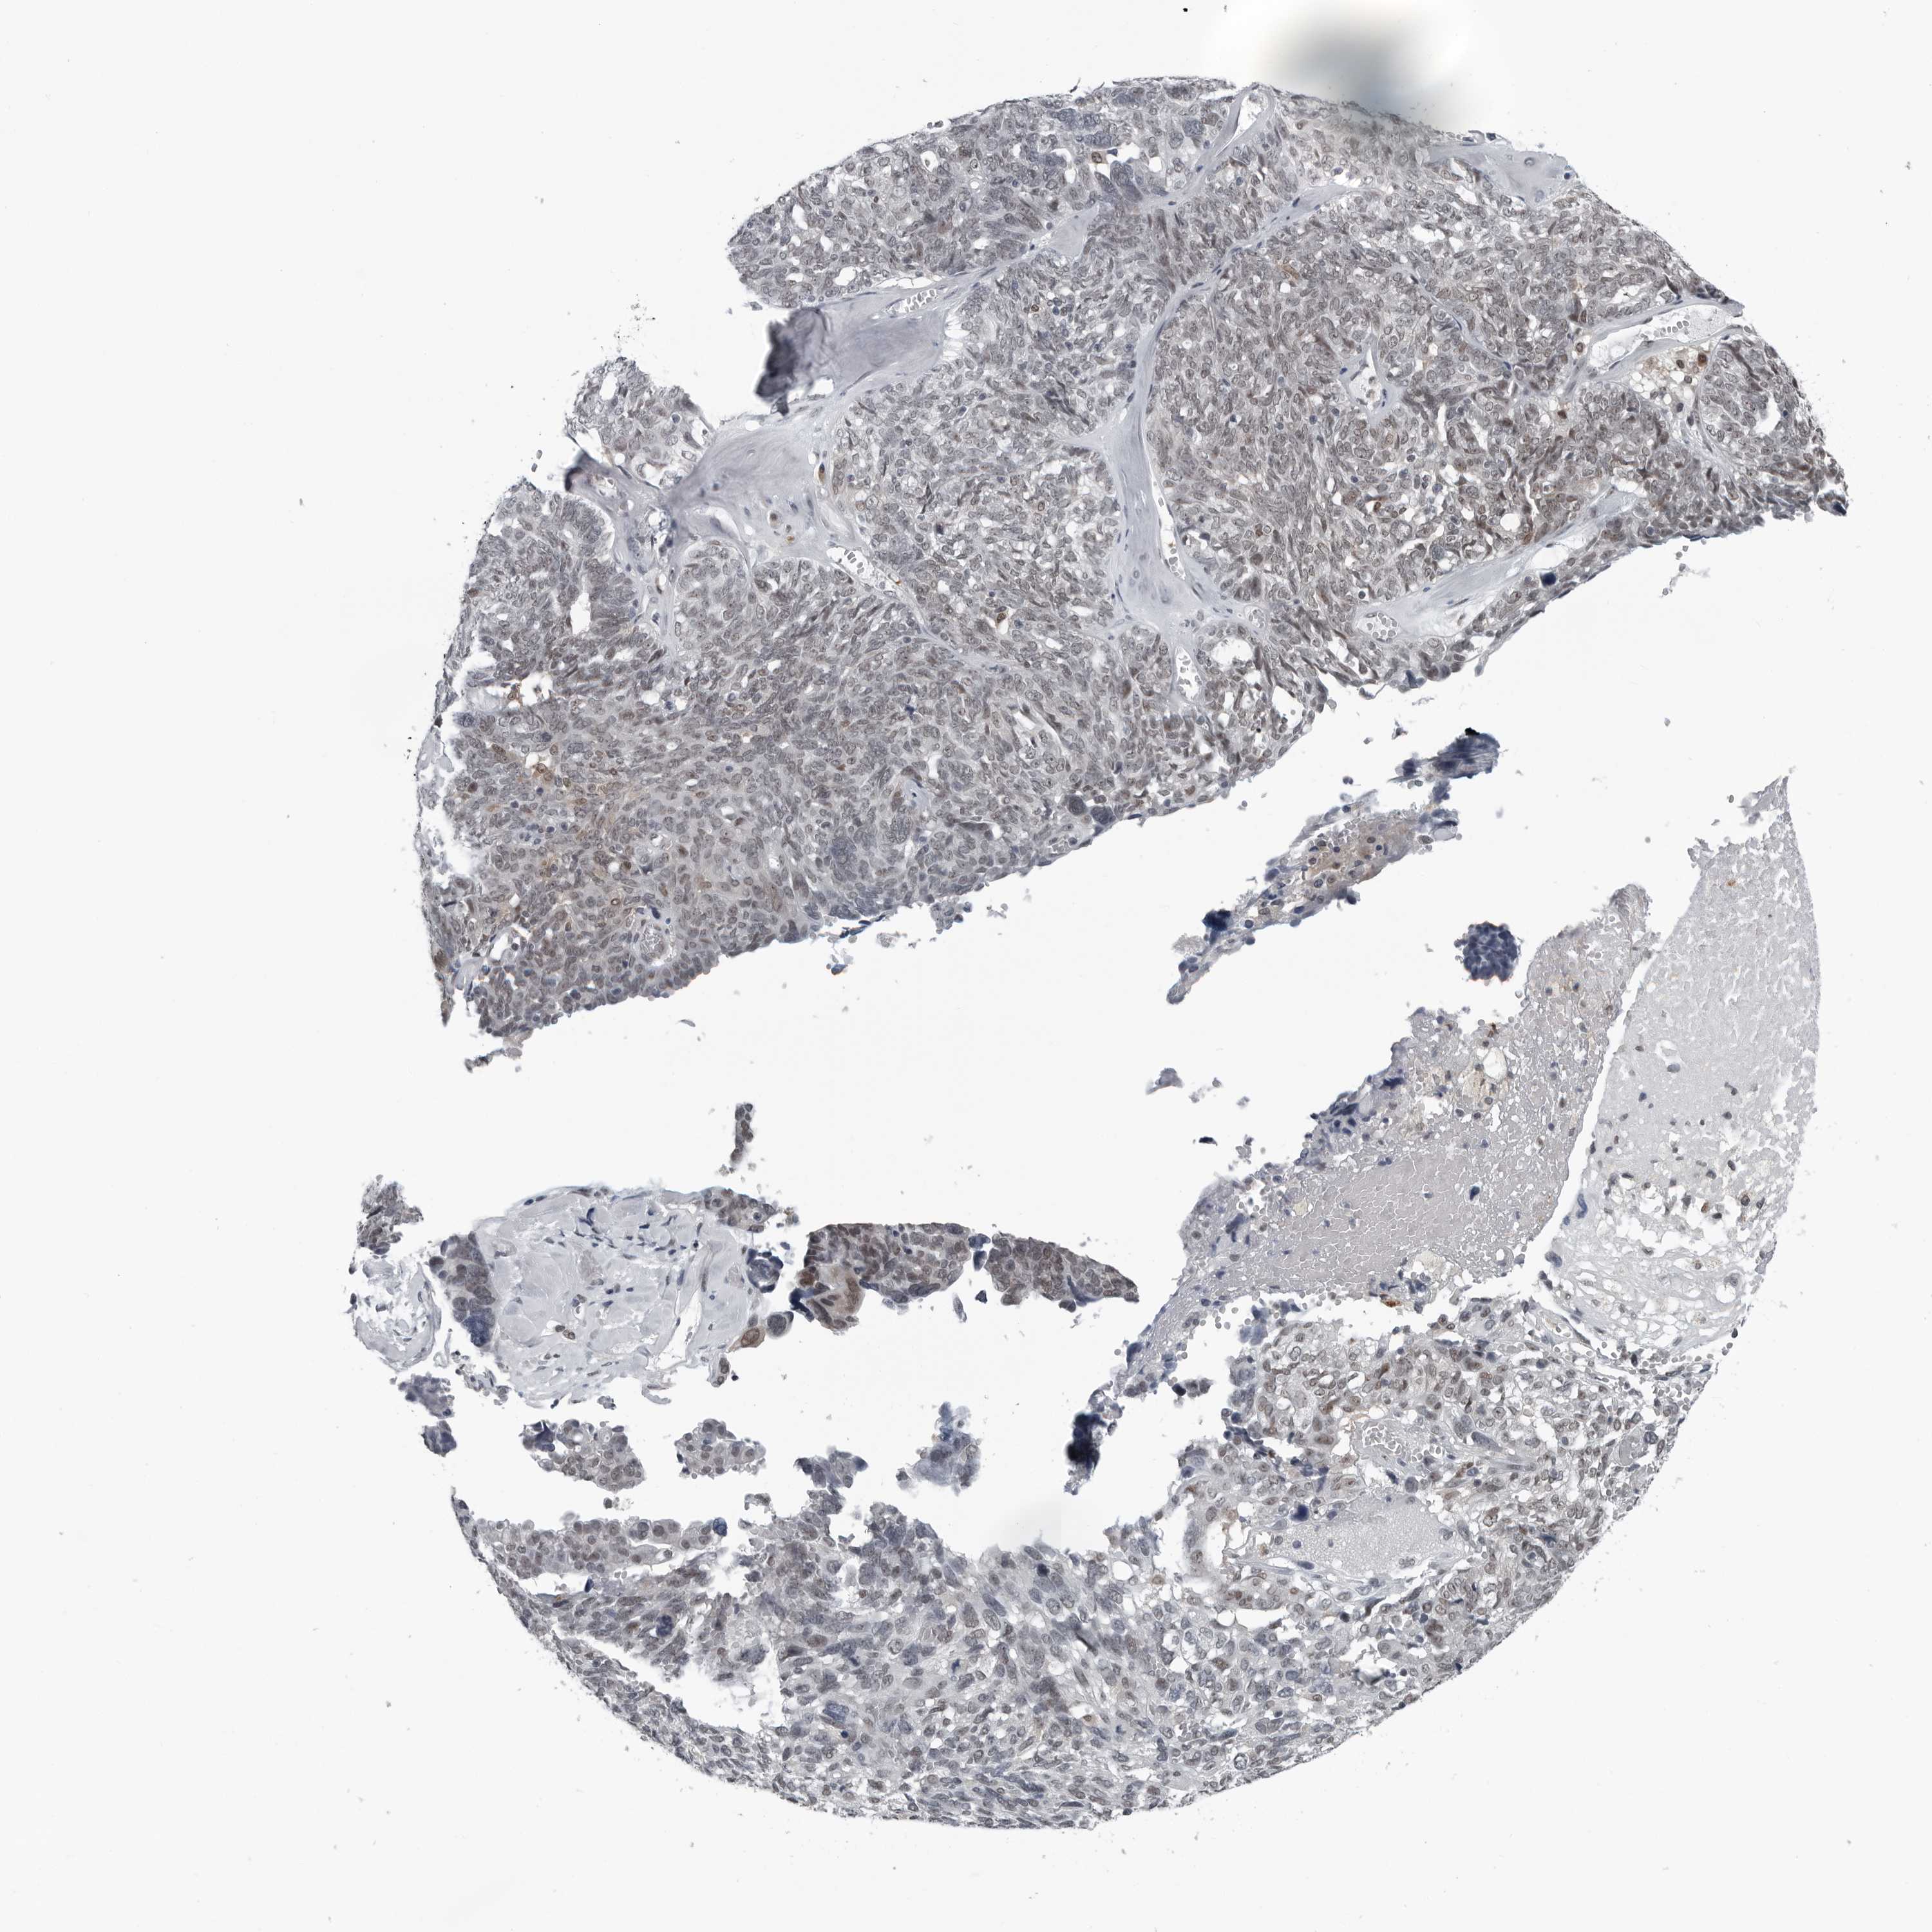

OVARIAN CANCER - Protein expressioni

A mouse-over function shows sample information and annotation data. Click on an image to view it in a full screen mode. Samples can be filtered based on level of antibody staining by selecting one or several of the following categories: high, medium, low and not detected. The assay and annotation is described here.

Note that samples used for immunohistochemistry by the Human Protein Atlas do not correspond to samples in the TCGA dataset.

Antibody stainingi

Antibody staining in the annotated cell types in the current human tissue is reported as not detected, low, medium, or high, based on conventional immunohistochemistry profiling in selected tissues. This score is based on the combination of the staining intensity and fraction of stained cells.

Each image is clickable and will lead to virtual microscopy that enables deeper exploration of all samples and also displays staining intensity scores, fraction scores and subcellular localization as well as patient and tissue information for each sample.

Antibody HPA017919

Antibody HPA019649

Antibody HPA027734

Antibody CAB006246

Cystadenocarcinoma, serous, NOS

Carcinoma, endometroid

Cystadenocarcinoma, mucinous, NOS

Carcinoma, NOS